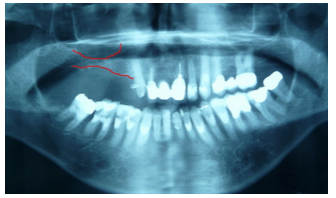

Paciente do sexo masculino, 58 anos se apresentou à clínica com histórico de perda de elementos dentais superiores do lado direito (figura 1). Após análise foi requerida radiografia panorâmica (figura 2). Constatada a pouca disponibilidade óssea na região, devido a pneumatização do seio maxilar, foi indicada a realização de cirurgia de elevação de seio maxilar.